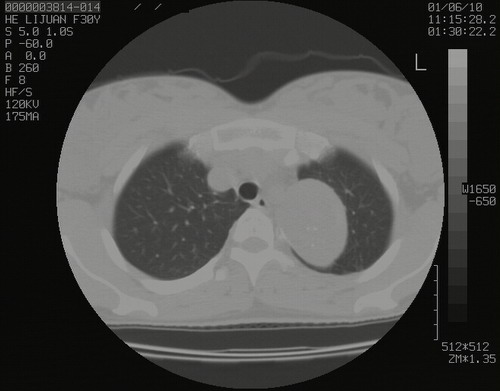

怀孕3个月时(2009-3至4月间),自述突感左侧前后胸疼痛1天,以前胸明显,随后偶感闷痛,余未见异

左肺尖脊柱旁沟肿块,境界清楚,边缘光滑,密度不均,内有多发点片状钙化,考虑良性肿瘤,骨软骨瘤或神经源性肿瘤可能,肺错构瘤不除外。

左后上纵隔见一类圆形肿块影,外侧边界清,密度不均匀,内可见点状钙化影,增强呈不均匀强化,考虑神经源性肿瘤可能。期待病理结果。